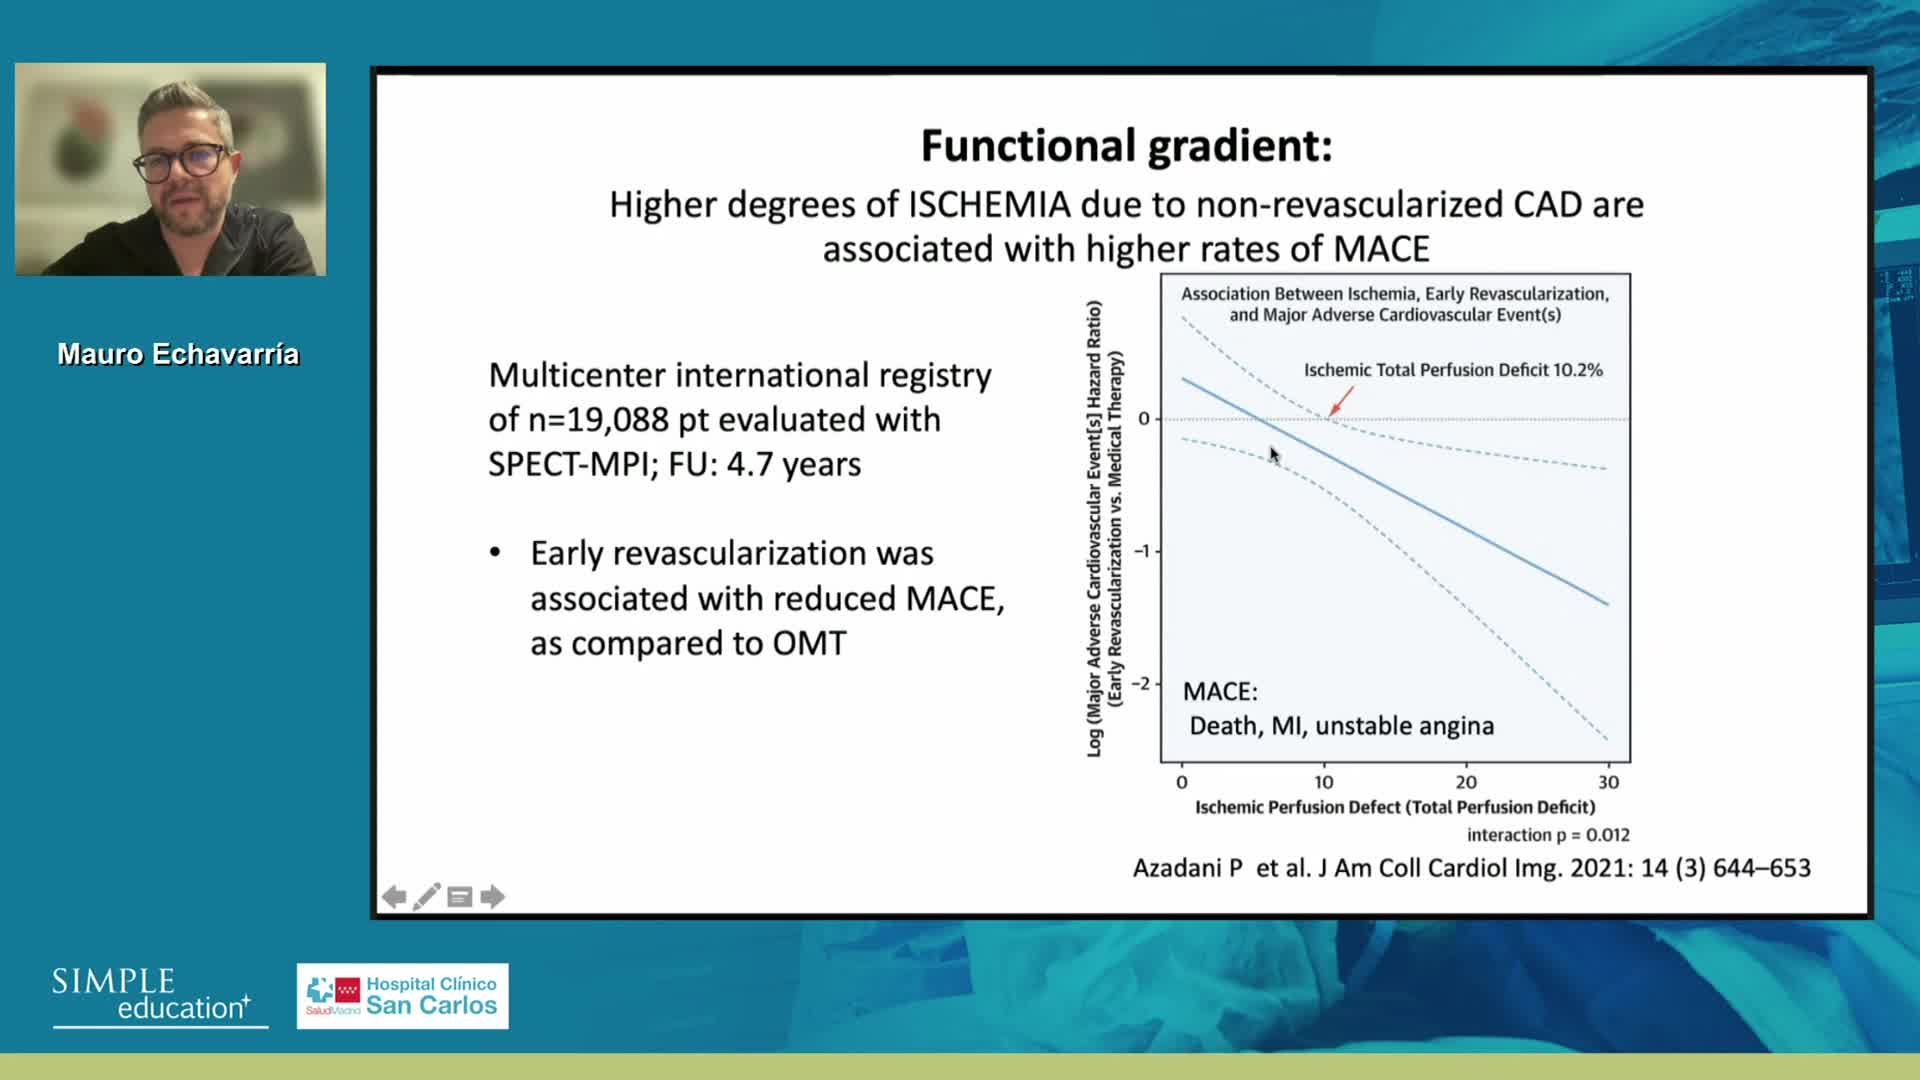

Welcome & Applied coronary physiology to plan and guide PCI-2023 EAPCI Consensus

Best practices and personalised medicine in complex PCI - Prof Javier Escaned

Essential steps for physiology-based PCI planning and guidance - Dr Allen Jeremias

Revascularisation in stable angina: a contemporary perspective - Dr Rasha Al-Lamee